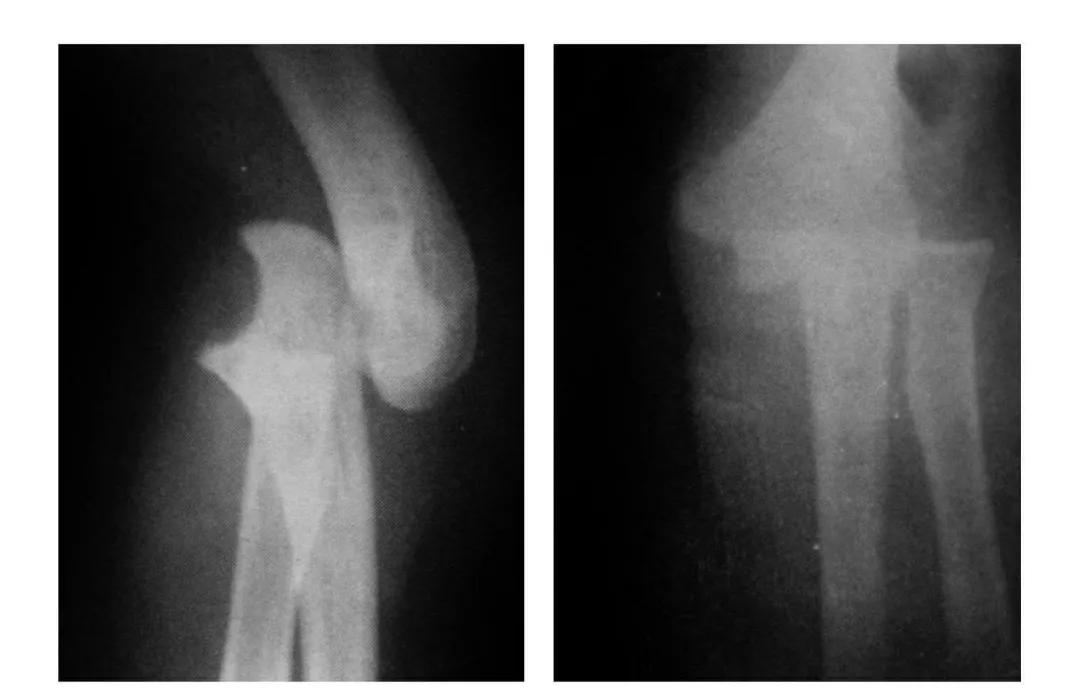

(二)部分骨折

本病亦称科-洛(Kocher-Lorenz)型骨折

例1:肱骨小头软骨面及其下方少量骨质呈“新月样”被剥脱,且向肘前上方移位并桡骨头前半部骨折。

例2:肱骨小头软骨面剥脱性骨折,致该小头新月状骨片被向前脱位的桡骨头顶向肘关节前上方,并尺骨干中段骨折(孟氏伸展型骨折)。

2

肱骨小头矢状面骨折

本病文献未见报道,即肱骨小头中部呈前后(矢状面)纵向骨折,将小头分为内外两部分。

本病因有明显的外伤史,即健侧小头正常,从而排除了先天因素。

例:肱骨小头矢状面骨折,折线波及外髁皮质骨折片,并鹰嘴突无移位骨折。